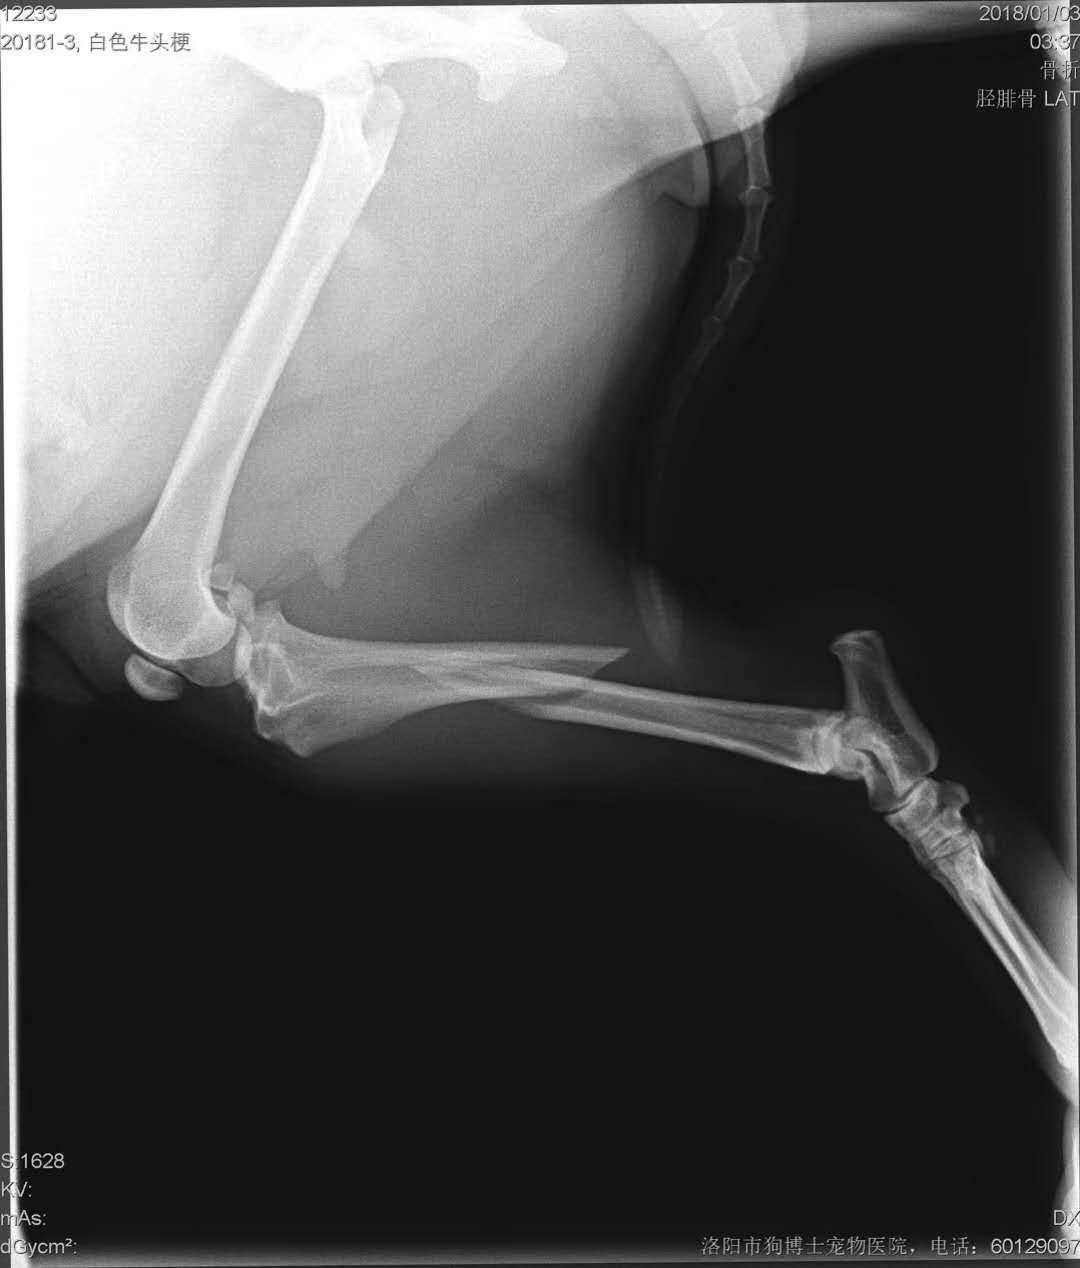

右后肢脛腓骨骨干骨折手術(shù)一例

右后肢脛腓骨骨干骨折手術(shù)一例:牛頭梗,骨頭,2歲,來自吉利,老客戶*而來,是一位偉大的媽媽,右后腿被籠子蹩斷,來院實(shí)施骨折內(nèi)固定手術(shù),手術(shù)順利,主人帶回家護(hù)理。